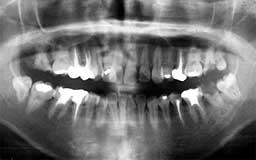

★ Pさん 52歳

年齢層をもう少し下げてみましょう。Pさんは来院時が52歳で、親知らずを除く喪失歯が

1本もなく健全そうにみえました。Oさん同様治療終了後の数年間にブランクがありました。

今から14年前の来院時にはメインテナンスを行うことの大切さがかなりはっきりわかってい

ましたので、それまでの経過を踏まえて少し強引にメインテナンスを勧めました。それ以降

はほとんど途切れることなくメインテナンスを継続されています。右の上顎第一大臼歯の1/3

だけ抜歯(ヘミセクション)していますので正確には現在残存歯数は27本と2/3ということ

になりますが、補綴(ほてつ)物も少なく10年後が楽しみな患者さんです。

| Pさん 初診時 52歳 男性 歯周疾患の進行傾向が随所に認められるが、年齢の割には比較的良好 |

Pさん 20年後 71歳 清掃状態は決して良好とはいえないが、20年間毎月メインテナンスを継続し良好な状態を保っている |